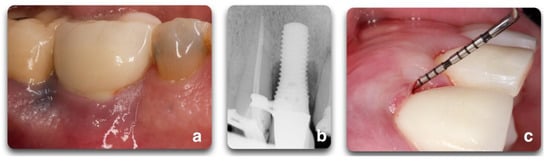

Figure 1.

Representation of peri-implant clinical parameters that, associated, can lead to a diagnosis of peri-implantitis. In the sequence above, BOP/Suppuration (a), radiographic bone level ≥ 3 mm (b) in combination with PD ≥ 6 mm (c).